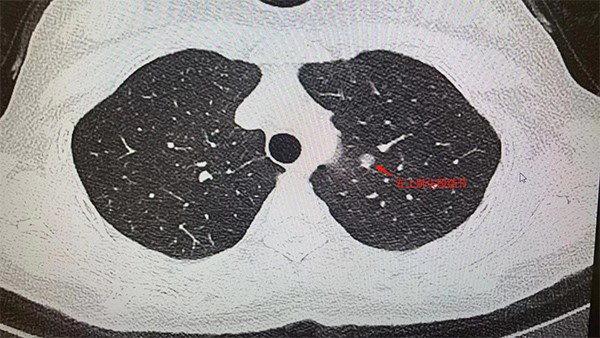

據了解,王女士今年5月在重慶市某三甲醫院做例行體檢時,低劑量胸部CT顯示:左肺上葉尖后段有7mm*6mm的磨玻璃結節,性質待定。醫生表示有肺癌可能性,建議進一步診治。肺結節這么小,到底切不切?10月24日,王女士來到重慶西區醫院胸外科主任姚珂門診隨訪。

姚珂介紹,結合影像學特征,王女士的肺小結節,惡性征象明顯。制定手術方案時,姚珂考慮到該患者病灶靠近主支氣管,位置較深,需要游離的血管較多,為保證精準切除病灶且最大程度保護患者肺功能,通過穿刺定位+CT三維重建引導,行單孔胸腔鏡下肺聯合亞段切術,最為合適。目前,手術取得成功。

患者胸部CT檢查圖片。重慶西區醫院供圖